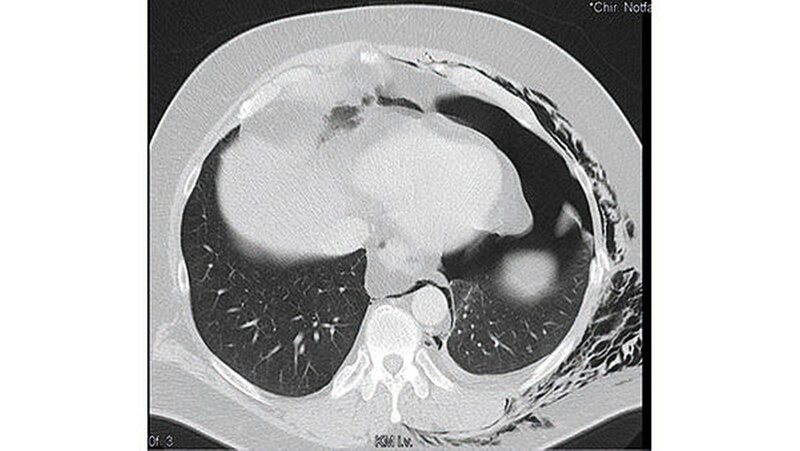

Die daraufhin durch die visceralchirurgische Abteilung durchgeführte Röntgen-Thorax-Aufnahme ergab keinen Frakturbefund im Bereich der Rippen bei ausgedehntem Weichteilemphysem. Bei weiterhin unklarer Diagnose und fehlenden radiologischen Korrelationen wurde auf nachdrückliche Indikation des MKG-Chirurgen eine Computertomografie des Thorax durchgeführt.

Diese zeigte nun Frakturen der siebten bis neunten Rippe links lateral, einen linksseitigen Mantelpneumothorax sowie ein ausgedehntes Weichteilemphysem mit Einstrahlen in den Hals, in den Rücken sowie in das Mediastinum (Abbildung 6).

Nach erneuter Vorstellung des Patienten bei den visceralchirurgischen Kollegen erfolgte nach Anlage einer Bülau-Thorax-Drainage die stationäre Aufnahme. Im Weiteren zeigte sich ein protrahierter Verlauf mit Hämatothorax und Pleuraempyem. Der Patient verblieb insgesamt dreieinhalb Wochen im stationären Aufenthalt bis zur restitutio ad integrum.